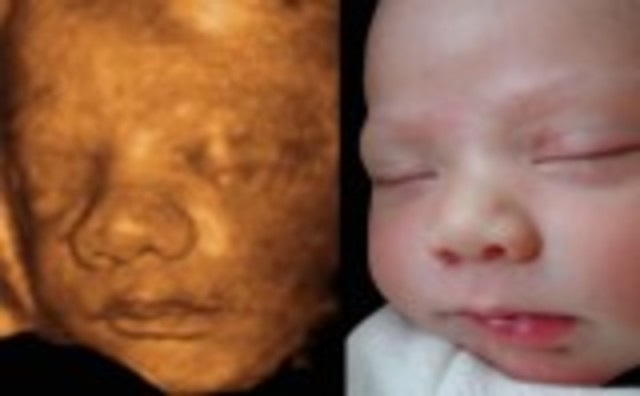

• Week 27: Eyes Can Open

Week 27: Eyes Can Open

This is the start of the third trimester and the baby now looks almost exactly how it will when it is born. The eyes can now fully blink.